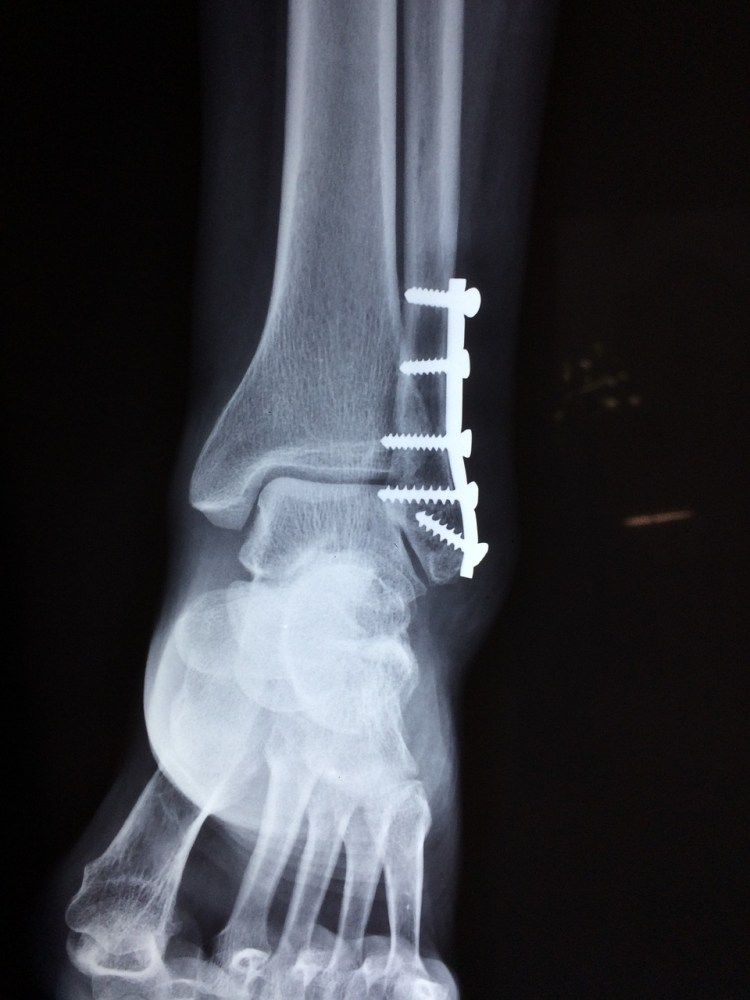

TRATAMIENTO DE FRACTURAS POR FRAGILIDAD

Las fracturas por fragilidad se producen por mecanismos de baja energía en pacientes mayores o con antecedentes de enfermedades que alteran el metabolismo óseo, su tratamiento es diferente debido al uso de implantes, placas y tornillos con características especiales para lograr la estabilidad necesaria para la consolidación ósea.